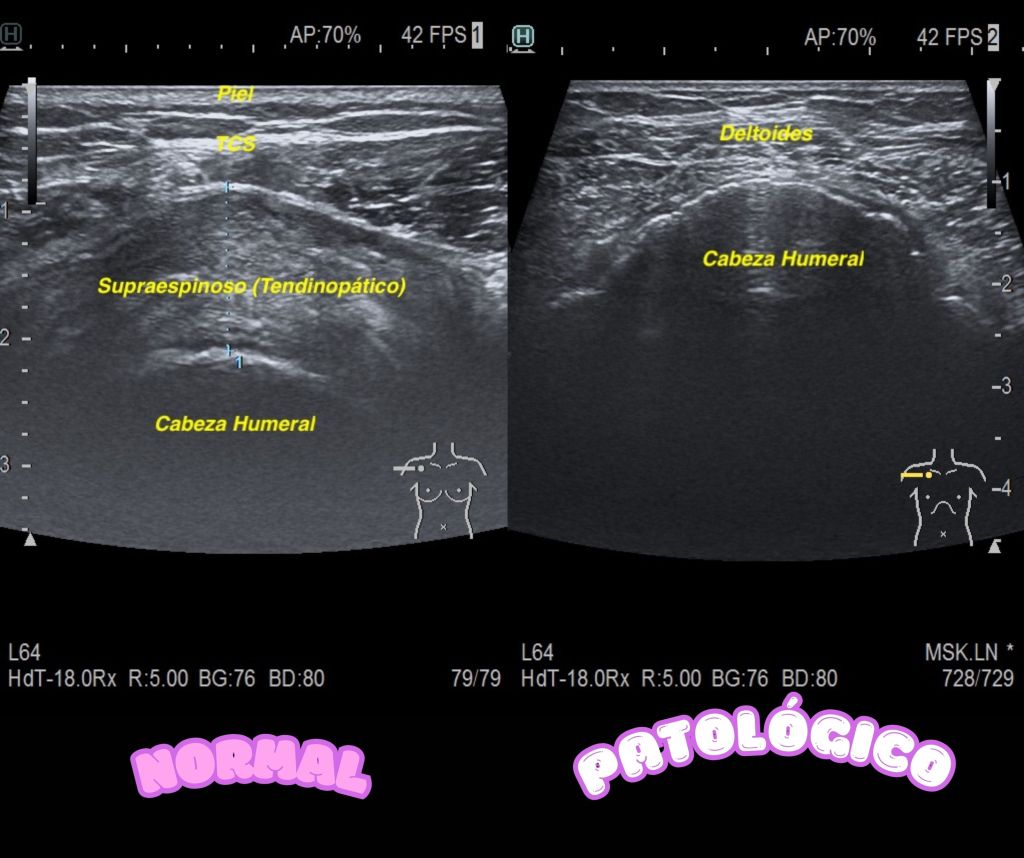

Siempre reconocer ecoanatomías normales o pseudonormales, en la imagen siguientes, ves a un tendón supraespinoso existente, aunque tendinopático y la imagen con la ausencia tendinosa por rotura del mismo.

Siempre muy útil, comparar ecoarquitectura, como dice María Leal en la Revista de ecografiafacil.com, en este caso, normal y patológica. Mira: